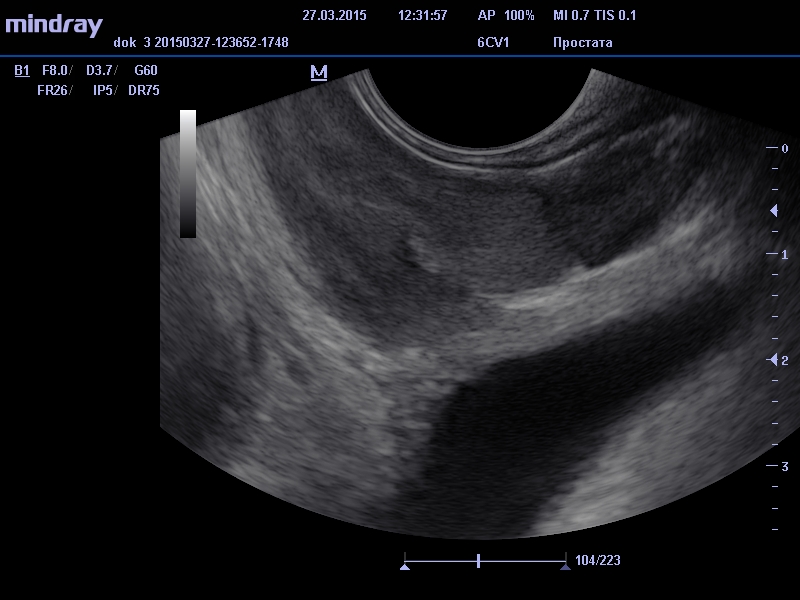

Этот способ диагностики имеет сокращенное название ТРУЗИ. Прибор, который вводится через анальное отверстие в прямую кишку, является ультразвуковым датчиком. Этот прибор очень чувствительный и благодаря ему врач, который проводит исследование, может видеть в органе малейшие отклонения от нормы, не видимые при трансабдоминальном способе исследования. При проведении исследования этим способом простату от датчика отделяет только стенка прямой кишки.

При проведении диагностики простаты мы определяем, какую форму и структуру имеет орган, и какой у него размер. Определение всех этих параметров входит в единую стоимость диагностики. Ультразвуковой современный и высокотехнологичный датчик выводит данные на экран, на котором видна реальная картина, исследуемого органа.